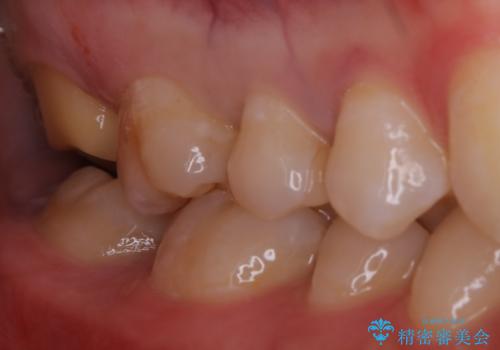

広範囲にわたる虫歯をセラミックで治療

- 他県より引っ越しをされたため、途中になってしまっている虫歯治療の続きをしてほしいと来院された患者様です。

痛み等の自覚症状はありませんでしたが、広範囲にわたる虫歯を認めたため、セラミッククラウンによる治療を行いました。

今回のケースでは、一番奥の歯の後ろ側に向かって虫歯が進行していました。一番奥の歯は元々の歯の高さが低いことが多く、被せ物が割れるリスクが増加したり、被せ物が外れやすくなる場合があります。歯牙切削量の少ないゴールドアンレーもご提案しましたが、セラミックをご希望されたため、今回はクラウンによる治療を行いました。